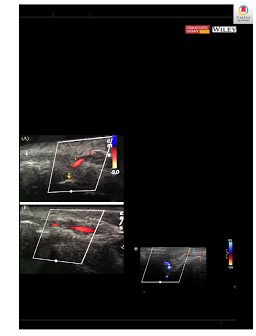

Management of dermal filler (vascular) complications using duplex ultrasound

Habib, S.M. (Sayed M.), Schelke, L., & Velthuis, P. (2020). Management of dermal filler (vascular) complications using duplex ultrasound. Dermatologic Therapy. doi:10.1111/dth.13461